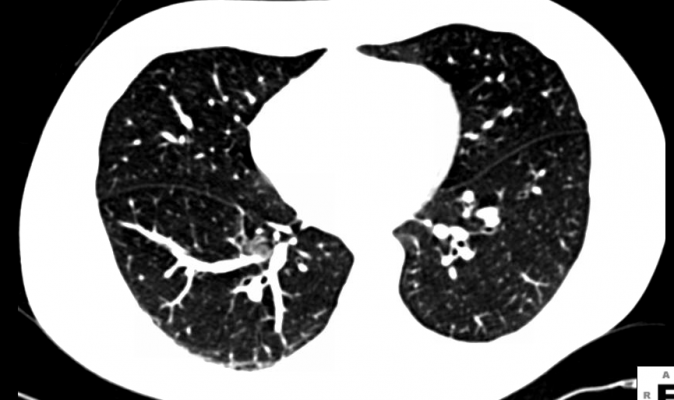

Lung cancer screening using low-dose CT (LDCT) is the only test ever shown to reduce mortality in high-risk smokers, the leading cause of cancer death in the United States. It does so cost effectively compared to other screening tests. Overdiagnosis is an expected part of any screening program and does not alter these facts. While medical science works to address overdiagnosis, the 18 percent overdiagnosis rate shown in this JAMA article is actually in line with that projected for other cancer screenings programs.

“Increasing the lesion size threshold to define a positive test from the 4-millimeter used in NLST to even 6-millimeter will reduce the false positive rate significantly, as shown by the I-ELCAP study earlier this year (2013). This will reduce additional diagnostic testing and should reduce overdiagnosis. This JAMA study is another piece of information to help arrive at a screening program, available across the country, that saves lives and improves quality of life,” said Ella A. Kazerooni, M.D., chair of the American College of Radiology Lung Cancer Screening Committee.